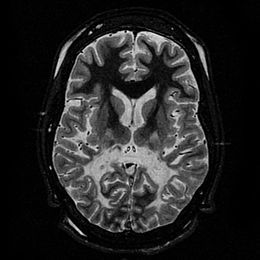

腎上腺腦白質失養症,又名ALD,是一種腦內去髓鞘化白質化的遺傳病,其通常分作兒童型腦白質化、青少年大腦型、腎上腺脊髓性神經病變型及女性異型合子病徵基因型。患者細胞的過氧化體在代謝較長的鏈脂肪酸時產生異常,尤其是C24、C26長鏈脂肪酸會異常堆積在大腦的白質和腎上腺的皮質內,進而侵蝕患者腦神經系統的髓鞘質,造成患者的髓鞘脫失,腦部的神經細胞因此就會被摧毀,進而妨礙神經的傳導。美國男性發生腎上腺腦白質失養症的機率為1:42,000;加上女性異合子基因型的發生率是1:16,800。而最近的報告則顯示為1/17000至1/25000。